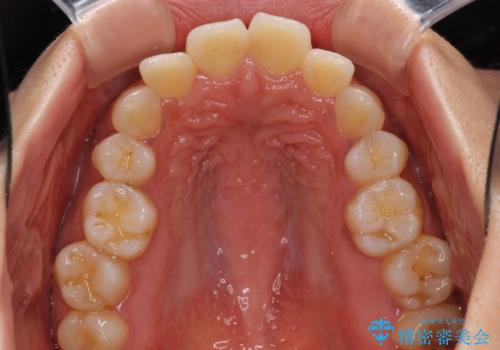

- 以前矯正治療をされていましたが、後戻りが起きたことを気にして来院された患者様です。

全顎的に認められた叢生を改善するため、インビザラインにて治療を行うこととしました。

前歯の叢生の改善を目的として、IPR(歯と歯の間を削る)と歯列全体の後方移動によって歯並びを整えることとしました。

毎日22時間の装着時間を守ってくださいましたが、ハイペースにマウスピースを交換することなく、慎重に治療を進めてくださったので、治療期間はやや長くなりました。

臼歯部も含め、叢生が綺麗に改善され、患者様には大変満足していただきました。